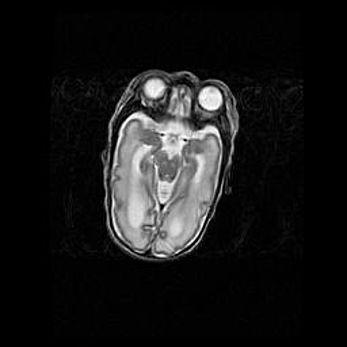

Мальформация Денди-Уокера. Киста задней черепной ямки.

Агенезия мозолистого тела.

Возраст: 2,5 месяца

Вес: 2420 г

Пол: женский

Окружность головы: 37 см

Срок гестации: 32 недели

Мальформация Денди—Уокера — редкий вид патологии ЦНС, представляющий собой врожденный порок развития каудального отдела ствола и червя мозжечка, ведущий к неполному раскрытию срединной (Мажанди) и латеральных (Лушка) апертур IV желудочка мозга. Для этогно синдрома характерна триада симптомов: гипотрофия червя мозжечка и/или полушарий мозжечка, кисты задней черепной ямки, гидроцефалия различной степени. В 70% случаев порок сочетается и с другими аномалиями головного мозга, в частности с агенезией мозолистого тела.